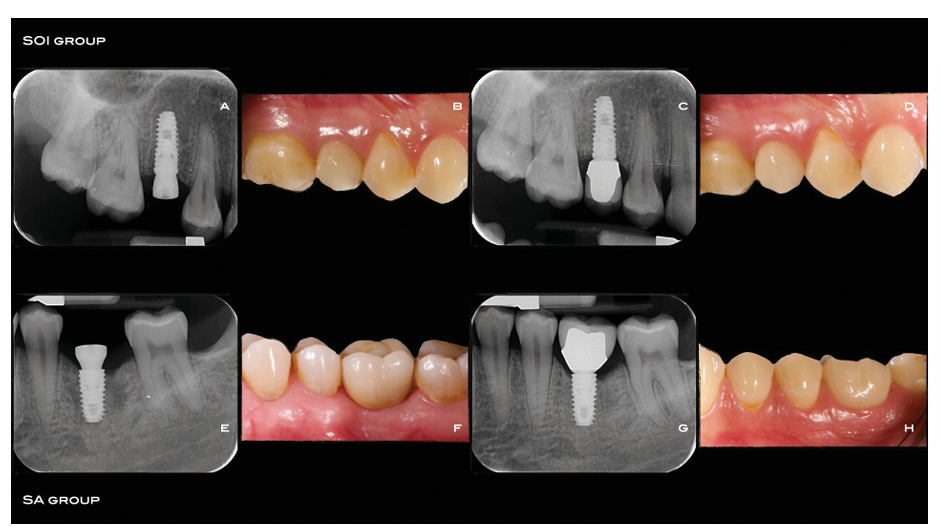

Circa 10 giorni prima dell'inserimento dell'impianto, tutti i pazienti hanno subito una sessione di igiene orale professionale. Tutti i pazienti hanno ricevuto terapia antibiotica profilattica: 2 g di amoxicillina 1 ora prima dell'intervento, o clindamicina 600 mg 1 ora prima dell'inserimento dell'impianto se allergici alla penicillina. Tutti i pazienti hanno sciacquato con collutorio di clorexidina allo 0,2% per 1 minuto prima di qualsiasi procedura chirurgica e sono stati trattati in anestesia locale utilizzando articaine con epinefrina 1:100.000. A seconda dell'anatomia del sito e delle preferenze del clinico, è stato ottenuto un accesso senza lembo o minilembi (lembo crestal senza incisioni verticali) (la stessa tecnica in ogni paziente). I siti di impianto sono stati preparati simultaneamente utilizzando punte coniche (800–1200 RPM) con abbondante irrigazione salina, secondo il protocollo di perforazione raccomandato dal produttore (kit 122 Taper, Osstem Implant) e densità ossea. Questa è stata valutata durante la fase di perforazione e classificata, in base all'esperienza del clinico, come: “duro”, “normale” o “morbido”. Gli operatori erano liberi di scegliere le lunghezze degli impianti in base alle indicazioni cliniche e alle loro preferenze. Se possibile, dovevano essere scelti due impianti della stessa lunghezza e diametro per ogni paziente. Gli impianti conici TSIII con superficie sabbiata e acido-reattiva (gruppo SA) o superficie SA modificata con agente tampone di pH (gruppo SOI) sono stati inseriti tramite un protocollo a una fase a livello osseo o leggermente subcrestale, con una coppia di inserimento minima di 30 Ncm. Gli impianti inseriti con una coppia inferiore dovevano essere esclusi da ulteriori misurazioni ISQ e lasciati guarire indisturbati per 4 mesi prima dell'applicazione della corona. La sequenza di trattamento è riportata nelle Fig. 2A-H.

Fig. 2 Da A a D: sequenza di trattamento nel gruppo SOI, posizionamento dell'impianto (A); consegna della protesi 12 settimane dopo il posizionamento dell'impianto (B); radiografia periapicale alla consegna della protesi (C); follow-up di 4 mesi (D). Da E a H: sequenza di trattamento nel gruppo SA posizionamento dell'impianto (E); consegna della protesi 12 settimane dopo il posizionamento dell'impianto (F); radiografia periapicale alla consegna della protesi (G); follow-up di 4 mesi (H)